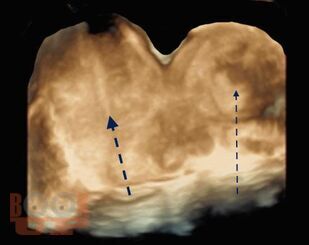

В учебно-методическом пособии приведен сравнительный анализ существующих методов лечения беременности в интерстициальном отделе маточной трубы и ангулярной беременности. Подробно изложен собственный запатентованный протокол лечения интерстициальной трубной беременности в зависимости от данных ультразвукового исследования в совокупности с уровнем ХГЧ в сыворотке крови беременной, разработанный авторами. Данный протокол позволяет на основании полученных диагностических данных выбрать оптимальный метод органосохраняющего лечения, определить методы последующего контроля состояния пациента.